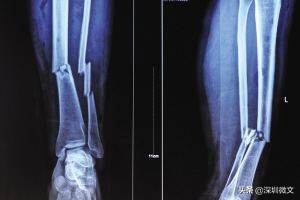

【X光:将人体骨骼投射到同一个平面上进行成像】

骨骼对于X光射线量的吸收较大,所以片子当中骨骼的颜色几乎是白色,而肌肉的吸收量较小,所以呈现为黑色。

举两个例子说明一下医生怎么通过“黑白色差”判断病情:

一、比方说某患者小腿出现明显骨折,那他骨折处对X光的吸收量就与周边骨干呈现出明显对比,骨折处就会出现一条明显的黑色裂痕。再者,医生也会通过白色“画成”的骨干是否有异常变形做判断。

二、部分患者并非因为骨折去拍片,而是因为骨头里进了异物。要想通过手术取出来,首先得准确判断异物在骨干精确到毫米的位置。医生怎么判断呢?异物在骨头内对X光的吸收量不同,那个点就会与周边骨干呈现出明显色差,一般是白色的骨干当中出现明显的黑点。通过这一异常医生就可以锁定异物位置。